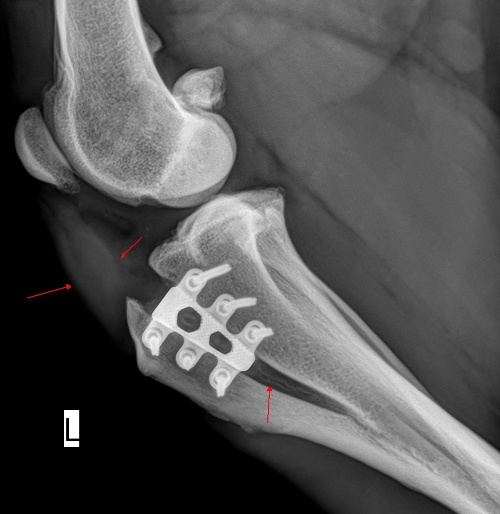

X-Ray image immediately after a TTA RAPID® Surgery →

Despite the inherent stability of the TTA RAPID® construct, the repair remains vulnerable until the osteotomy has filled and consolidated.

During the initial six weeks post-operatively, strict leash exercise is crucial, limited to 5-10 minutes per session. Hydrotherapy is encouraged during this period. Between six weeks and the three-month follow-up, radiograph exercise may be gradually increased but should still be performed on leash.